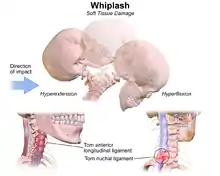

The exact injury mechanism that causes whiplash injuries is forceful sudden hyperextension followed by hyperflexion of the cervical vertebrae, mainly spraining the nuchal ligament and the Anterior Longitudinal Ligament respectively. A whiplash injury may be the result of impulsive retracting of the spine, mainly the ligament: anterior longitudinal ligament which is stretched or tears, as the head snaps forward and then back again causing a whiplash injury.[16]

There are four phases that occur during "whiplash": Initial position (before the collision), retraction, extension and rebound. In the initial position there is no force on the neck it is stable due to inertia.[23] Anterior longitudinal ligament injuries in whiplash may lead to cervical instability.[24] They explain that during the retraction phase that is when the actual "whiplash" occurs, since there is an unusual loading of soft tissues. The next phase is the extension, the whole neck and head switches to extension, and it is stopped or limited by the head restraint. The rebound phase transpires as result of the phases that are mentioned.

During the retraction phase, the spine forms an S-Shaped curve, and this caused by the flexion in the upper planes and hyperextension at the lower planes and this exceed their physiological limits this phase the injuries occur to the lower cervical vertebrae. At the extension phase, all cervical vertebrae and the head are fully extended, but do not surpass their physiological limits. Most of the injuries happen in C-5 and C-6.[25]